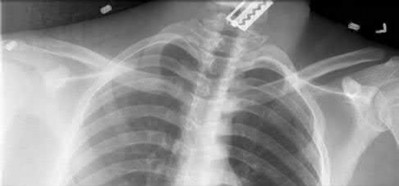

1024) An 18-year-old football player crossing the field to make a catch is hit on the shoulder and upper chest by the tackler and falls to the

ground with immediate pain throughout the shoulder region. The emergency department physician obtains the radiographs, CT scan, and 3-dimensional reconstructions seen in Figures 118a through 118e. What is the next step in management?

1. Obtain an MRI scan of the shoulder.

2. Place the arm in a sling for comfort and treat the injury nonsurgically.

3. Perform closed reduction in the emergency department.

4. Perform closed reduction in the operating room.

5. Perform open reduction using Kirschner wires to hold the joint reduced.

Corrent answer: 4

The player has sustained a posterior sternoclavicular dislocation. The CT scans show the medial end of the clavicle in close proximity to the aorta. An MRI scan will add no diagnostic information and might delay treatment. Nonsurgical management of an anterior sternoclavicular dislocation is often appropriate, but given the proximity of the clavicle to the aorta and airway, reduction of the dislocation is recommended to prevent vascular injury. While reduction is indicated, performing the reduction in the emergency department is not recommended because of the vascular injury or the need to perform an open reduction. Performing the procedure in the operating room with a thoracic surgeon available is recommended. Usually a closed reduction is stable, but if open reduction is necessary, Kirschner wires should be avoided to avoid the chance of migration of the implants.